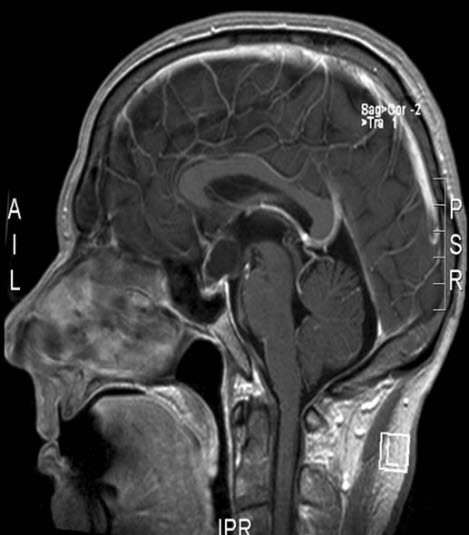

Kraniopharyngeom, sagittalt snitt

Gjengitt med tillatelse av Radiologisk avdeling, Universitetssykehuset Nord-Norge